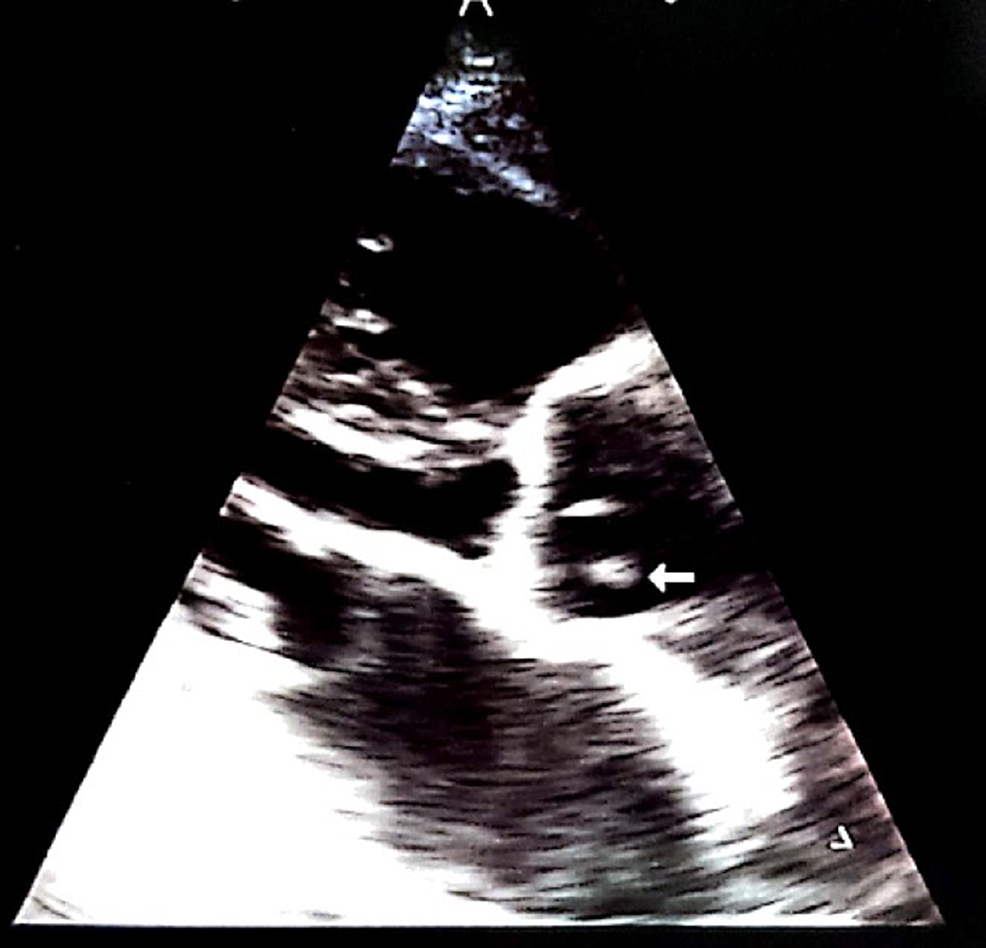

An echocardiogram revealed no obvious clots in the left ventricle. However, it was significant for mobile vegetations on the non-coronary cusp of the aortic valve (Figure 2). A grade I diastolic dysfunction with a global ejection fraction of 58% was also noted.